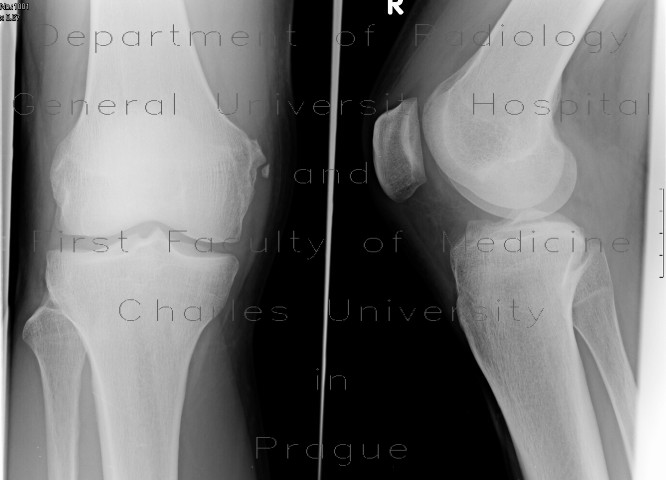

Pellegrini Stieda Lesion : Pellegrini Stieda lesion | Image | Radiopaedia.org / The origin of this tissue is controversial.. It is a common incidental finding on knee radiographs. One presumed mechanism of injury is. Ossification in or near the tibial collateral ligament (medial femoral collateral ligament) adjacent to the margin of the medial femoral condyle. Dr ammar haouimi and dr behrang amini et al. Most of the cases of pellegrini stieda lesions are not symptomatic, and pellegrini stieda syndrome is said to exist when the lesion becomes symptomatic i.e.

Ossification in or near the tibial collateral ligament (medial femoral collateral ligament) adjacent to the margin of the medial femoral condyle.

Most of the cases of pellegrini stieda lesions are not symptomatic, and pellegrini stieda syndrome is said to exist when the lesion becomes symptomatic i.e. The pellegrini stieda syndrome is when there is associated pain and movement restriction and is a combination of the imaging and clinical findings. One presumed mechanism of injury is. Is the presence of a radiological finding of calcification on the medial side of the knee as a consequence. Pain and restriction of movements.